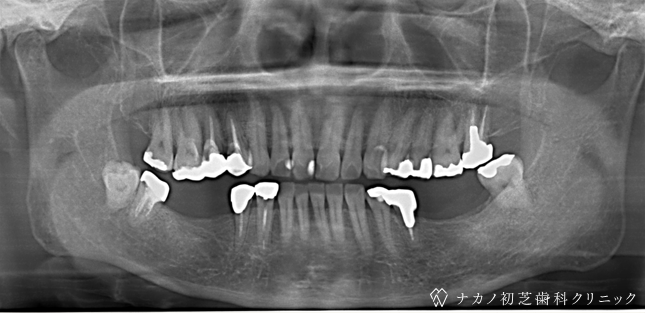

インプラント・7本 (60代男性)

-

BEFORE

AFTER

年齢 60代男性

治療内容 インプラント治療7本(骨造成の併用)

インプラント治療とは、歯を抜いた所にチタン製の人工歯根を埋入し、その上に歯を入れる方法です。骨を増やすことで、より審美的に治療が出来ました。費用 1本 400,000円(税込 440,000円)

リスク・副作用

腫れ・疼痛・違和感を感じるなどの症状を生じることがあります。